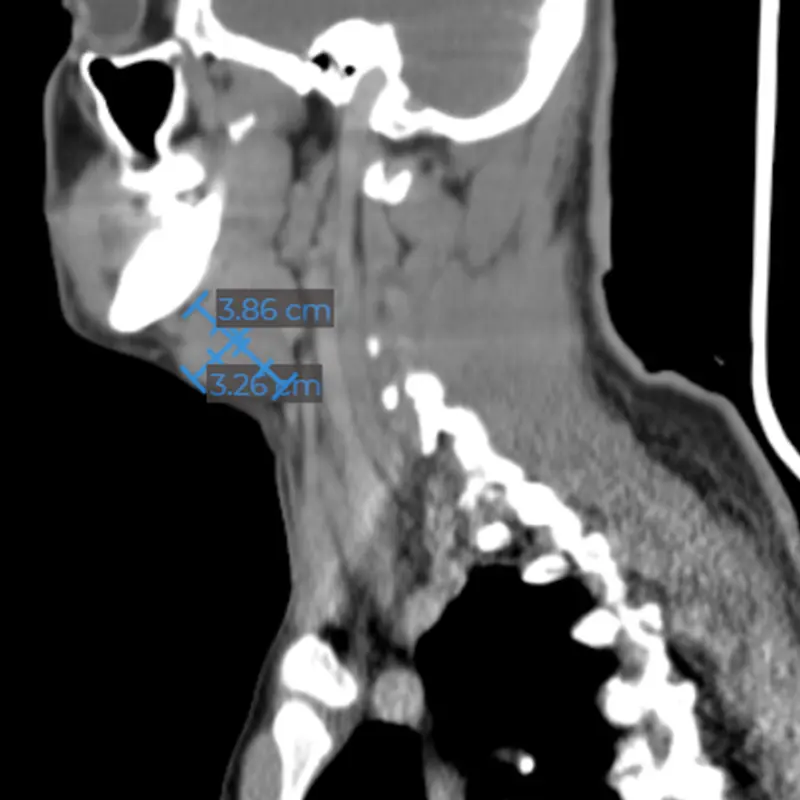

Apnea del sueño (por obstrucción maxilofacial)

Una de cada 10 personas adultas en México podría padecer apnea obstructiva del sueño, siendo este un factor de riesgo de hipertensión y enfermedades vasculares, los hombres presentan dos veces más probabilidad de padecer este problema.

Los neumólogos subrayan la necesidad de crear conciencia sobre la importancia de atender la apnea obstructiva del sueño, ya que, al ser común, las personas minimizan el problema por la creencia de que roncar es normal.

Los síntomas de la apnea son relativamente fáciles de identificar consisten en un ronquido continuo y ruidoso y pausas en la respiración al dormir.

La investigación del Síndrome de Apnea Obstructiva del Sueño, ha demostrado científicamente que la cirugía ortognática y/o de estructuras de los maxilares es una solución definitiva a este problema en pacientes que presentan deformidades dentofaciales.